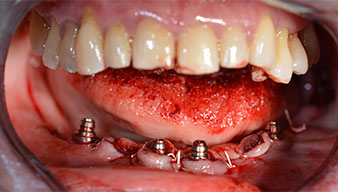

Направи се скенер с триизмерна компютърна томография (CBCT, Planmeca), за да се подпомогне планирането и да се намалят рисковете. Той показа, че качеството и количеството на наличната кост са достатъчни за операцията и имедиатното възстановяване, използвайки Fast & Fixed метод. Следвайки протокола за тази концепция, имплантите са поставени на 35, 32, 42 и 45 позиция. Ангулирането на дисталните импланти до 45° промени профила в задната зона и осигури по-голяма поддръжка в многоъгълната зона (Фиг. 3).

След отстраняване на частичното обеззъбяване в долната челюст, алвеоларният гребен е разкрит от 37 до 47.

Изходът на долночелюстния нерв е първоначално идентифициран като ограничена анатомична структура и, след това, кортикалната кост на гребена е загладена с прав наконечник и голям борер с розовиден профил (Фиг. 4).

Светлината увеличава контраста в оралната кухина и подобрява визуалното възприятие. Обратният наконечник и S-11 прав наконечник на W&H са с външно охлаждане, което е голямо предимство по отношение на физиологичния разтвор, който достига точно, където трябва и може да бъде впоследствие редуциран, ако е необходимо. Правите и обратни наконечници могат да бъдат разглобени, което е силно препоръчително от гледна точка на хигиената и стерилизацията. Поставени са четири импланта SKY с размери 4.0 x 14 мм.